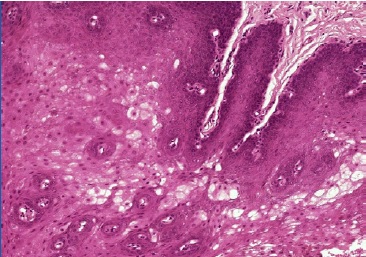

The post-operative observation was conducted 15 days after (Figures 2 and 3). The specimen was preserved in a 10% buffered formalin solution and sent for histopathological examination, which identified superficial parakeratosis, promirev nent acanthosis of the squamous epithelium, and areas with prominent intracellular edema. These findings are consistente with our diagnosis of oral WSN (Figures 4 and 5). No genetic study was performed. WSN is a benign condition that requires no treatment.

Figure 4 Microscopic features of the specimen retrieved from the right buccal mucosa biopsy (hematoxylineosin staining, 40x) showing superficial parakeratosis and prominent acanthosis of the squamous epithelium.

Figure 5 Microscopic features of the specimen retrieved from the right buccal mucosa biopsy (hematoxylin-eosin staining, 100x) showing prominent intracellular edema.

The WSN histopathological findings are a thickened stratified squamous epithelium showcasing parakeratosis, cytoplasmatic clarification, and vacuolization due to the intracelular edema of the stratum spinosum layer, nuclear condensation, very mild inflammatory infiltrate, if present, and eosinophilic perinuclear aggregates.3,5,10,13 These appear to be unique to WSN and represent the aggregation of keratin tonofilaments, as shown in ultrastructural studies by electron microscopy.1,3,10,13 The value of cytology alone in the diagnosis of WSN is controversial. Cohen et al.1 found their results on exfoliative cytology to be unspecific and, therefore, of limited diagnostic value. In turn, Martins Filho et al.12 confirmed the presence of perinuclear eosinophilic condensation on their smears, adding weight to Messadi et al.’s25 claims that the characteristic perinuclear eosinophilic condensations are more visible on smears than on conventional histopathological examinations. Lajolo et al.26 have suggested using exfoliative cytology with KRT4 and KRT13 gene sequencing instead of oral biopsy as the diagnostic algorithm of choice, as it is a non-invasive approach, thus preferable for younger patients.